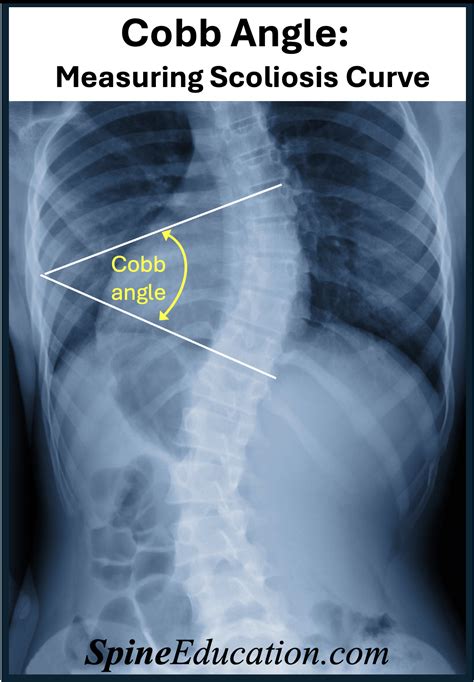

The spine is designed to be straight when viewed from the back. However, in cases of scoliosis, the spine develops an abnormal sideways curvature. The Angle Of Cobb is the primary tool used to measure the severity of this deviation. Originally developed by Dr. John Robert Cobb in 1948, this technique remains the most widely accepted method for longitudinal studies and clinical assessment. It relies on standard radiographic imaging (X-rays) to project the spine onto a two-dimensional plane, allowing the physician to draw lines that intersect to create the angle in question.

To determine the measurement, a radiologist or surgeon must follow a precise, standardized protocol. The accuracy of this measurement is vital, as small discrepancies can sometimes lead to different treatment recommendations. The process involves identifying the most tilted vertebrae at the top and bottom of the spinal curve.

• Identifying End Vertebrae: The professional selects the topmost and bottom-most vertebrae that tilt the most toward the center of the curve.

• Drawing Lines: A line is drawn parallel to the superior endplate of the top vertebra and another line is drawn parallel to the inferior endplate of the bottom vertebra.

• Intersection: Perpendicular lines are then drawn from these two lines until they intersect. The resulting angle between these lines is the Angle Of Cobb.